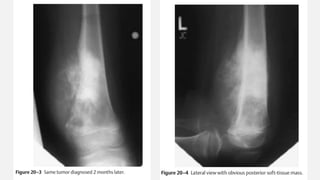

EWING’S SARCOMA FEMUR

• An otherwise healthy 20-year-old male developed a sudden increasing pain in his right

femur. The pain is so severe that he is unable to walk, needs crutches, and requires

high doses of narcotics. The pain awakes him from sleep. There is no history of

associated trauma. He has not noticed any pal- pable mass nor antecedent pain in his

right femur. Of note, he had a prior anterior cruciate ligament reconstruction on his

right side, but this procedure was done in the distant past and is unrelated to any of

his pain. He has actually had excellent rehabilitation from that procedure and tolerated

the procedure well. He has had no associated fever or chills. White count and

infectious laboratory work reveal normal sedimentation rate and C-reactive protein

(CRP). Anteropos- terior and lateral femur (Fig. 19–1 and Fig. 19–2) films show a lytic

lesion of the middiaphyseal region with a sun burst periosteal reaction. Magnetic

resonance imaging (MRI) (Fig. 19–3 and Fig. 19–4) revealed a soft tissue mass with a

right peritumoral inflammatory zone associated with it. The mass measures

approximately 5 × 4 × 3 cm. Computed tomogra- phy (CT) scan shows cortical

erosions as well. A chest CT also was performed, showing no obvious pulmonary

metastases. A bone scan was ordered as well (Fig. 19–5).

Orthopedic Oncology by Ernest Conrad

Thieme